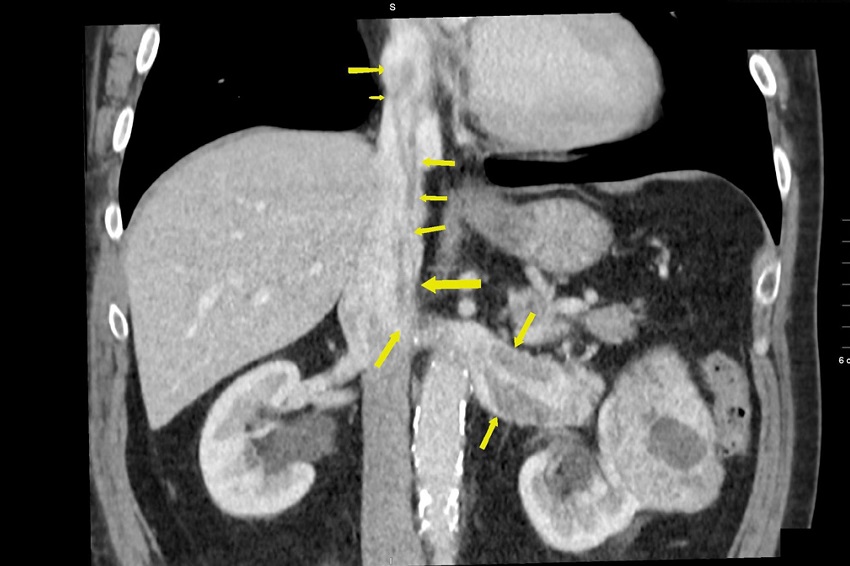

Two patients operated at our clinic in January 2018 were a 55-year-old female and 61-year-old male who were recently diagnosed with RCC, both with stage T4NxM0 (T4 tumor grossly extends into the vena cava above the diaphragm, Nx regional lymph nodes cannot be assessed, and M0 indicates no distal metastasis), who were scheduled for radical right nephrectomy with IVC thrombectomy. All patients were preoperatively evaluated with routine blood analyses, chest X-ray, transthoracic echocardiography (TTE) computerized tomography (CT) and contrast venacavography. Preoperative CT and TTE revealed the tumor extension into the IVC up to the RA for male patient and supradiaphragmatic portion of IVC in female patient (Figure 1).

The operation was performed by our team of vascular surgeons. Cardiac surgery team was also assembled assigned to the care of the patient, because the original plan was to do the sterno-laparotomy and partial veno-venous bypass. Following the induction of general anesthesia, internal jugular central line was inserted. In addition, a multiplane TEE probe was placed in the esophagus. Initial TEE examination of the heart confirmed the normal cardiac structures and function without a patent foramen ovale. TEE study was performed with emphasis on the hepatic veins, IVC, right side of the heart, and pulmonary arteries (PAs). The tumor was well visualized in the IVC extending proximal into the RA for male patient and supradiaphragmatic portion of IVC in female patient (Figure 2).